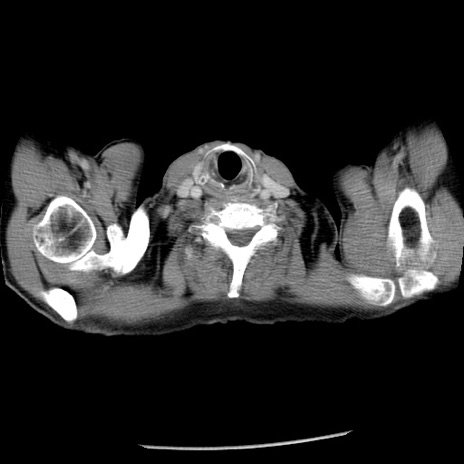

冠状断像

【症例】80歳代男性

【主訴】嘔吐

【現病歴】昨晩2回嘔吐あり、今朝になっても嘔吐あり。来院。

【既往歴】胃潰瘍

【身体所見】意識清明、BT 37.6℃、BP 166/95mmHg、HR 100bpm、SpO2 97%、腹部:平坦・軟、腸蠕動音聴取良好、圧痛なし。

【データ】WBC 21900、CRP 1.46